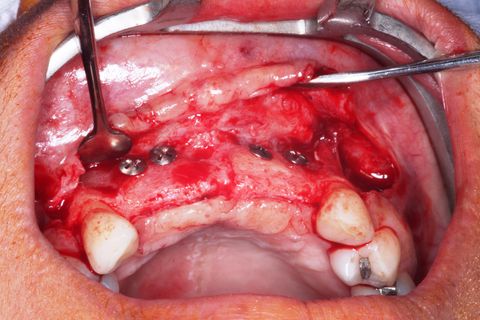

Procedimento cirúrgico. Incisão Supra crestal, intra-sulcular e oblíqua na distal dos caninos

Área receptora. Descolamento mucoperiosteal. Notar o defeito ósseo côncavo na região de incisivos

fixação do bloco ósseo com parafusos de cabeça expandida Neodent.

Sutura